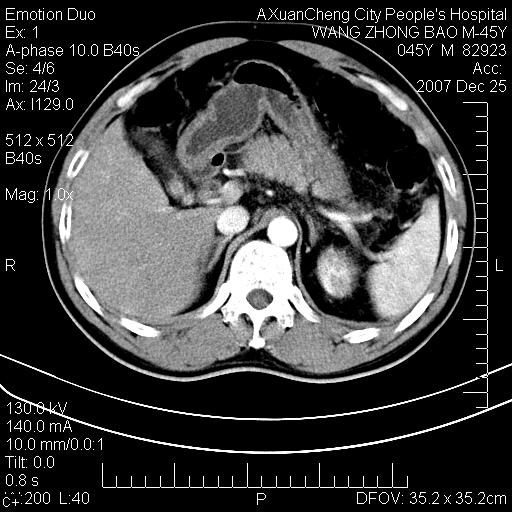

以下是引用卜一在2007-12-25 14:07:00的发言:[br]胰头钩部略增大,与十二指肠壶腹部关系密切,其内明显见软组织密度肿块,明显强化,但肠壁较光滑 柔软。考虑:炎性增生!建议消炎后复查!待除外壶腹部腺癌!

以下是引用zjzjr在2007-12-25 13:35:00的发言:[br]考虑正常的十二指肠乳头部,建议胃镜检查.

以下是引用qiuleiyu在2007-12-25 18:14:00的发言:[br]胰腺增大,周边渗出改变,肾前筋膜明显增厚,示少量积液.胆囊壁毛糙,周边少许渗出,胆总管壁厚,异常强化,然扩张不明显.结合病程急短;考虑;胆管炎,胆囊炎,胆源性胰腺炎可能大,请结合实验室检查及随访.

以下是引用lisihao在2007-12-25 14:23:00的发言:[br]急性水肿型胰腺炎[br]依据:1、胰腺弥漫性肿大,边缘稍毛糙;[br] 2、双侧肾周筋膜增厚,尤以左侧为甚(重要征象)[br] 3、双侧后胸膜增厚(刺激性炎症);[br] 4、结合病史,查血尿淀粉酶应该可以确诊。